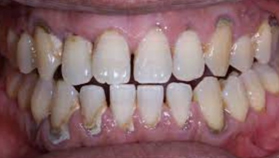

歯石が多く沈着し歯周病が進行している状態